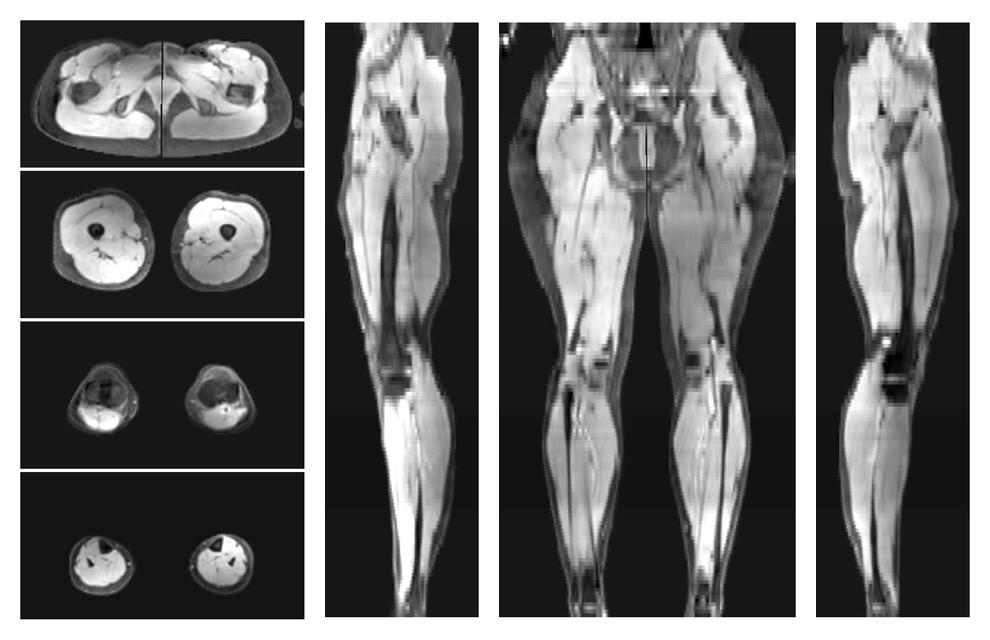

• Water only signal

The water part of the acquired multi-echo spin echo data.